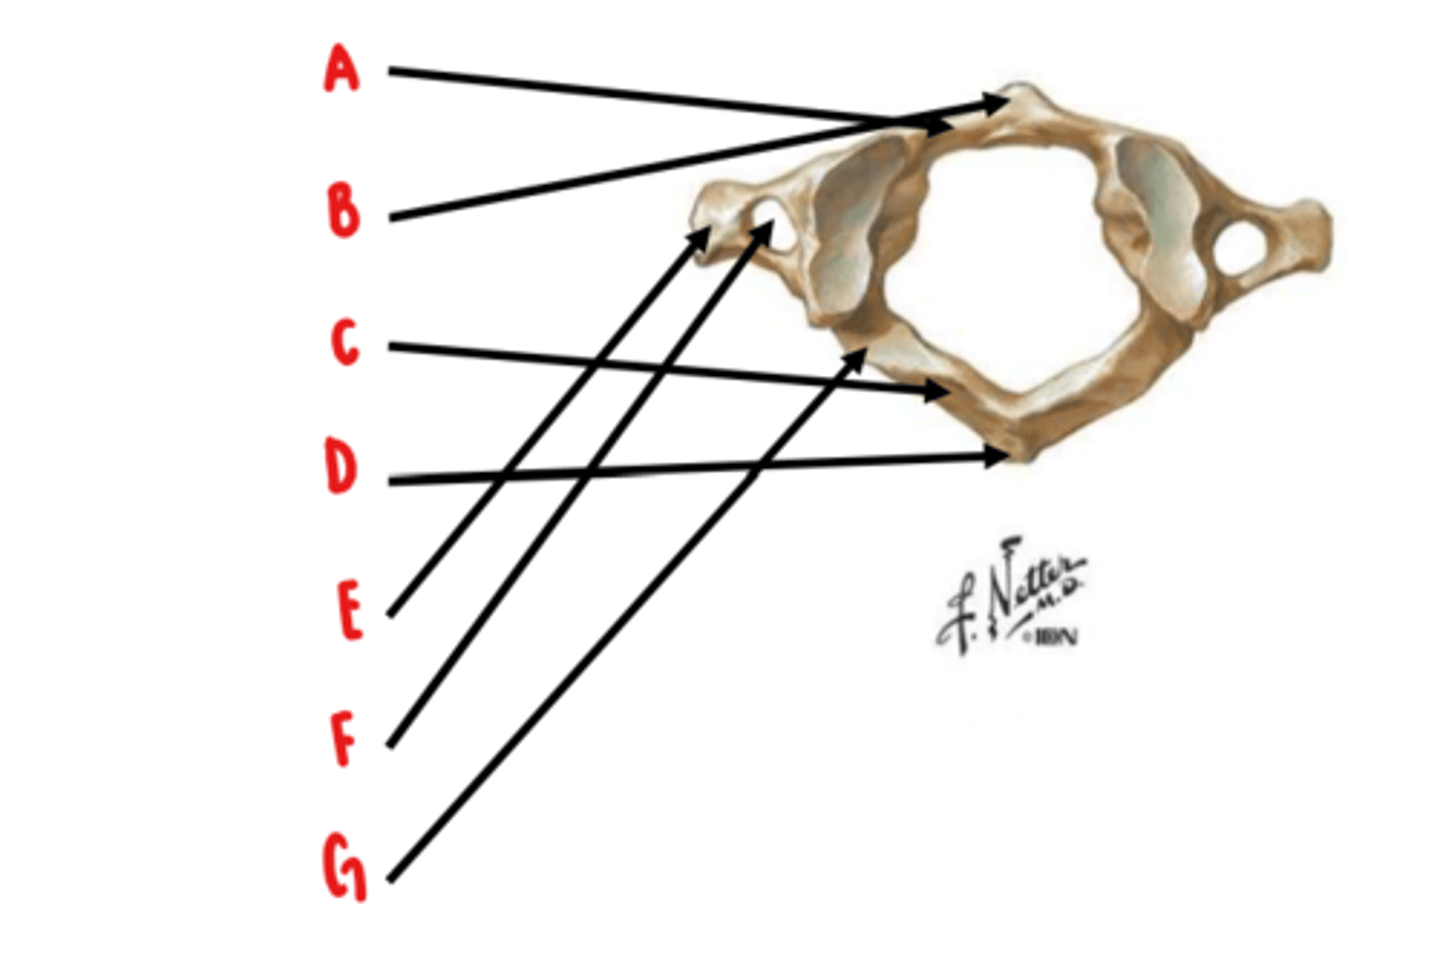

Atlas (C1)

What vertebrae is this?

anterior arch

Identify A

anterior tubercle

Identify B

posterior arch

Identify C

posterior tubercle

Identify D

transverse process

Identify E

transverse foramen

Identify F

groove for vertebral artery

Identify G